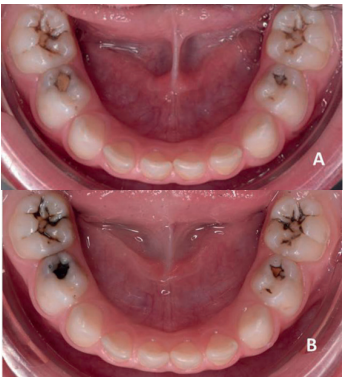

- En ambas denticiones, tanto en dientes anteriores como posteriores2 (Figuras 1 y 2).

oclusales de los molares temporales. B: Dos semanas después de la aplicación del FDP se observa la tinción oscura de las zonas afectadas.